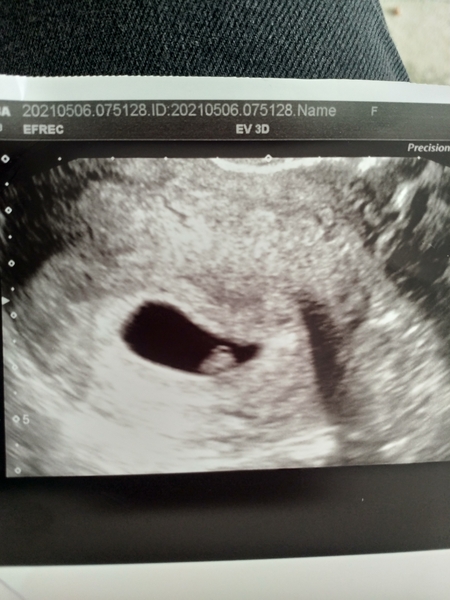

Hi all had a wee scan today at 6+5 everything looking good, heartbeat is nice and strong. I have my booking in app at 9+2. Still very nauseous and tired, also really thirsty. But like some have said, water totally bags me up and makes me feel worse. Soda seems to be ok as long he burping gives a little release 🙈

@Moo37 brilliant news! I'm 6+3 today, nice to see what a little bean looks like on a scan at this time! 😊❤

@Moo37 lovely scan pic 💕